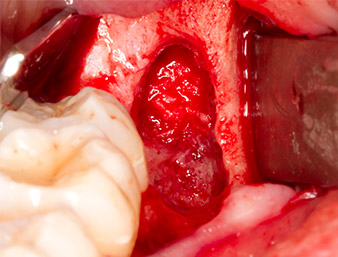

To expose the root remnant with as little trauma as possible to the tissue, a further instrument was used (Piezomed S2) that is primarily indicated for preparing the lateral window in augmentations of the sinus floor. The diamond-coated ball was additionally used to smooth sharp bone edges (Fig. 6 and 7). All the Piezomed attachments were used with the relevant automatic default setting without booster function.

Piezomed S2

Fig. 6: The root remnant is carefully exposed with a diamond-coated spherical instrument (Piezomed S2), bone edges are smoothed.

root remnant 38

Fig. 7: The root remnant 38 (LL8) is well exposed in its alveole for subsequent removal.